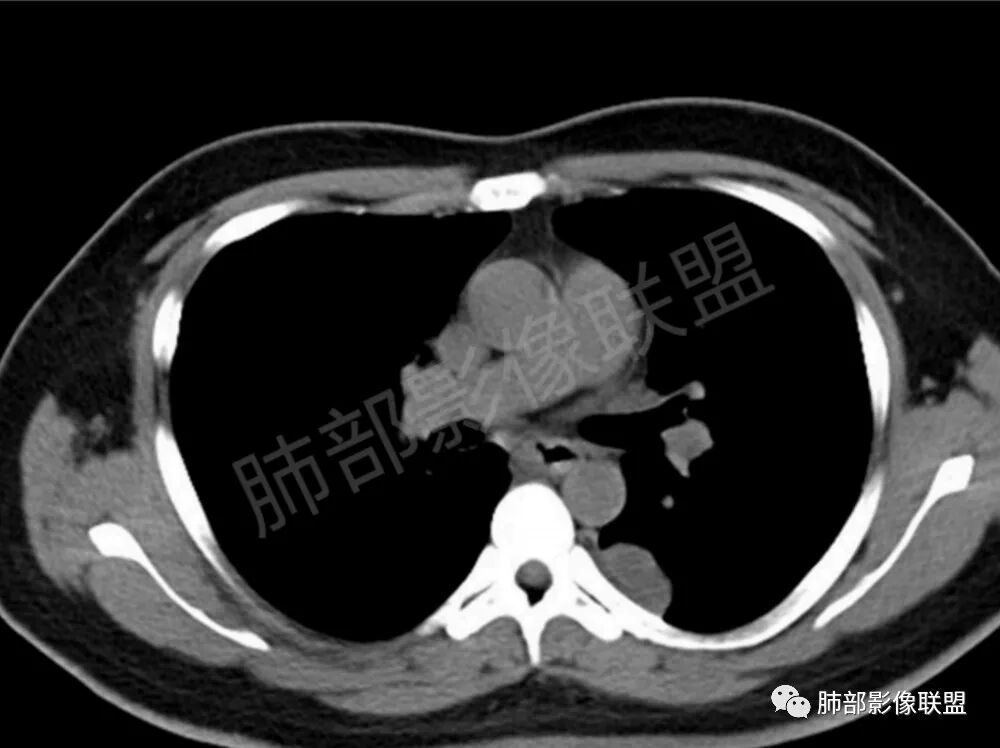

两肺多发结节性,大部分位于胸膜下,部分结节周围可见晕征。局部结节内可见扩张的支气管,纵隔淋巴结大,脾大,22岁男,HIV阳性,常规先考虑隐球菌。鉴别淋巴瘤,结核,马儿。

男,22,半年前咳嗽伴少痰,查HIV阳性,痰查TB阳性,既往有肺部斑片影伴空洞、纵隔淋巴结肿大、脾大。SCC、CA50、CA199、FER增高,此次胸部CT:两肺多发结节影,部分沿血管束分布,部分贴胸膜下,大小不一,密度不一,部分较散、边缘模糊,部分较实、圆钝、周围模糊晕,部分结节有支气管进入穿行自然,部分结节有血管分支自如通过。考虑HI∨相关淋巴增殖类病变,淋巴瘤?LYG?鉴别PC、TB。

青年男性,半年前咳嗽,HIV阳性,结核DNA阳性,肿标糖类抗原和铁蛋白增高。外院影像有纵隔淋巴结增大伴脾大,肺部病灶空洞。现在影像:肺内多发沿支气管分布(有支气管充气征,长轴沿支气管分布)及胸膜下分布(平行于胸膜)的大小不等结节,个别伴有空洞,双侧腋窝淋巴结肿大。纵隔图片不够,是否还有淋巴结肿大未知,脾脏未显示。

1、HIV相关淋巴瘤,有HIV阳性,有纵隔及腋窝淋巴结肿大,肺内病灶沿支气管分布(中轴淋巴间质)及胸膜下分布(周围淋巴间质),有脾大,这个是必须要考虑的。但是原来的影像是肺斑片影伴空洞,又有疑问,需要穿刺明确。

支气管血管束和小叶间隔分布,其实也就是沿淋巴间质分布,这个好理解

影像学缺乏特征性,以支气管血管周围、胸膜下及双肺下叶周边多发结节影最多见,结节易坏死形成空洞,伴有游走性和多变性的特征,结节周围可有磨玻璃样晕征,有时也可见单发结节影、薄壁的囊状阴影或弥漫性浸润影。肺门、纵隔淋巴结肿大少见, 可见胸腔积液和气胸。